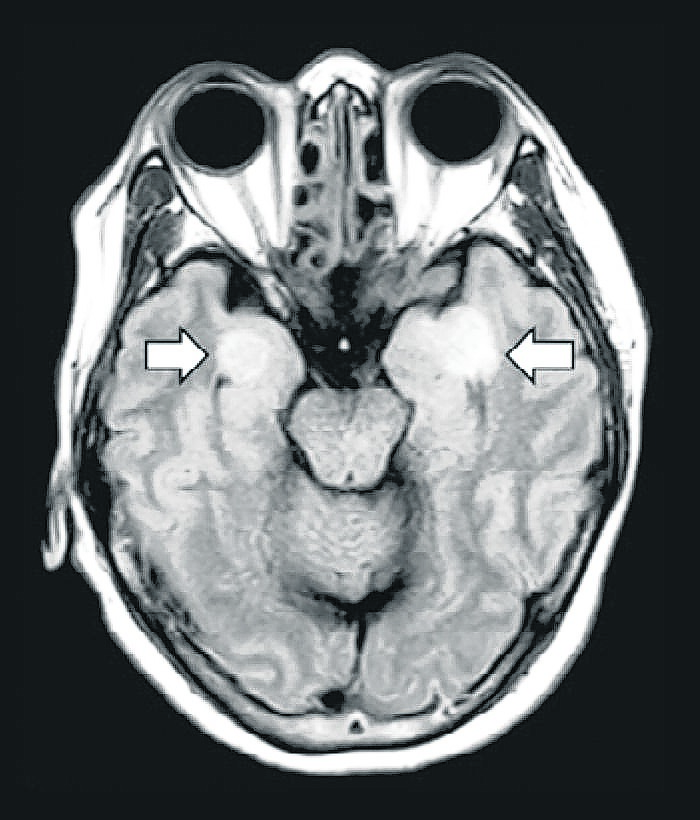

Los estudios realizados en medio de una lucha que es por la vida, muestran trazos de la presencia del virus en todos esos órganos o sistemas. Biopsias, radiografías, resonancias magnéticas, modelos en 3D y escáneres dan cuenta de un daño brutal pero misterioso en sus causas.

Otro conjunto sorprendente de síntomas en pacientes con covid-19 se centra en el cerebro y el sistema nervioso central, pues se han visto pacientes con encefalitis inflamatoria cerebral, con convulsiones y una “tormenta simpática”, es decir una hiperreacción del sistema nervioso simpático que causa síntomas similares a las convulsiones y es más común después de una lesión cerebral traumática.